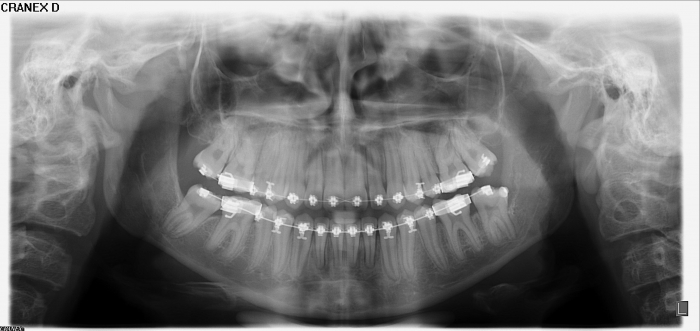

Rx Panorâmico - Pré cirúrgico, com os elementos 37 e 47 impactados - Clínica Cliniface

Rx Panorâmico - Pré cirúrgico, com os elementos 37 e 47 impactados